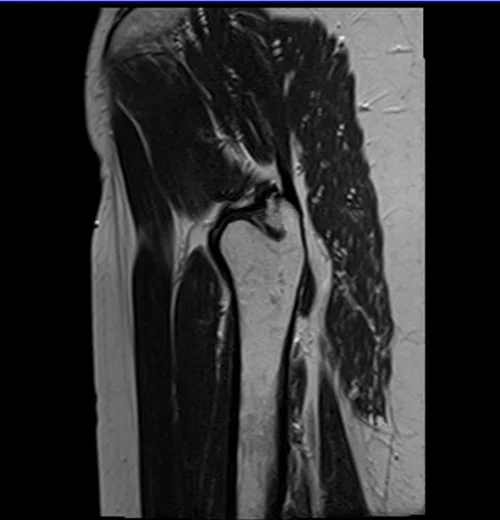

Unlock MRIMaster Offline & Ad-Free for $10